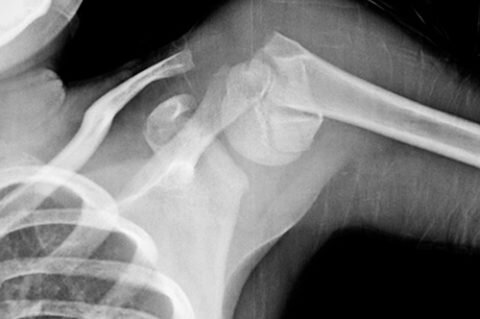

Первая медицинская помощь при переломе плечевой кости на этом этапе заканчивается, все остальные мероприятия осуществляет только врач. По результатам рентген снимков в двух проекциях и наличия сопутствующей симптоматики ставиться точный диагноз, после чего назначается лечение.

Травма плеча может образоваться на любом участке плечевой кости, но в частых случаях их локализация отмечается в проксимальном отделе. При этом повреждается целостность структуры хирургической шейки или суставной головки.

Переломы плеча относятся к ряду одних из самых сложных травм, имеющих много особенностей, что обуславливается анатомической структурой плечевой кости.